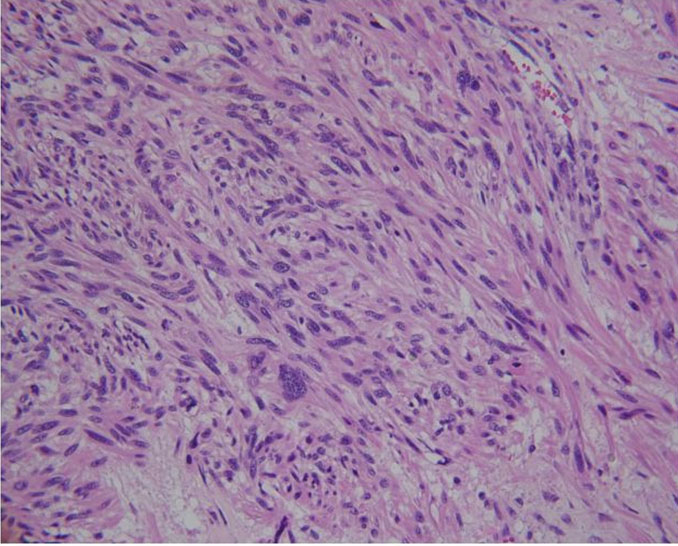

The patient underwent right radical inguinal orchiectomy with excision of the spermatic cord. A paratesticular mass grossly measuring 9.7 × 7 × 6.5 cm was excised and sent for pathologic examination. Microscopy revealed a malignant spindle cell neoplasm consistent with leiomyosarcoma associated with areas of hypercellularity measuring 24 mitoses per 10 high-power fields (0.1735 mm2) and positive surgical margins (Figure 2). There was evidence of lymphovascular involvement of the testicular vein without invasion of the vas deferens or the spermatic cord stroma (Figure 3 and Figure 4). Immunohistochemistry was diffusely reactive for calponin, caldesmon, desmin, and smooth muscle actin immunostains. The final pathologic stage classification was pT2 (pTNM; American Joint Committee on Cancer, 8th edition). Staging CT scans of the chest, abdomen, and pelvis were negative for metastatic disease. Following multidisciplinary discussion, adjuvant radiotherapy was offered but deferred after careful consideration of this patient’s case. Scrotal immobilization during radiotherapy is challenging and limits the delivery of a targeted, reproducible radiotherapy dose. Furthermore, an extensive postoperative radiotherapy field would be required. The patient remains disease-free at one month of follow-up after surgery, with plans for continued surveillance.

Figure 4: H&E stain, 200× demonstrating paratesticular leiomyosarcoma inside lumen of testicular vein.